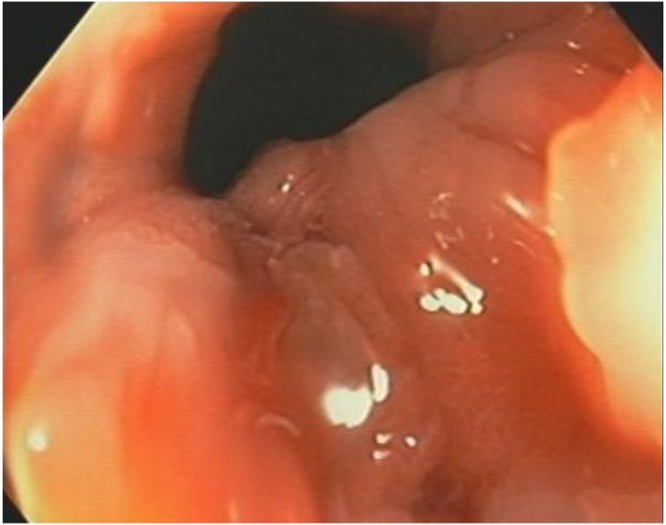

A 48-year-old female self-presented to the Emergency Department complaining of 3 weeks of anal pain which was initially being treated as haemorrhoids. There was no significant family history of malignancy. She was subsequently referred to a colorectal surgeon for persistence of symptoms and described pain in the anus on sitting and pain during the passage of a motion. Examination revealed a sore lump in the anal canal. Colonoscopy and examination of the anus under anaesthesia showed an 8 mm plaque on the dentate line that was biopsied (Fig. 1). Histopathology described a small cell carcinoma, with mucosal glands lined by high grade dysplastic columnar epithelial cells in keeping with small cell carcinoma adenocarcinoma – 20% of neoplastic cells stained for Ki67.

Fig. 1.

EUA + colonoscopy showed an 8 mm plaque just below dentate on left side of anal canal.